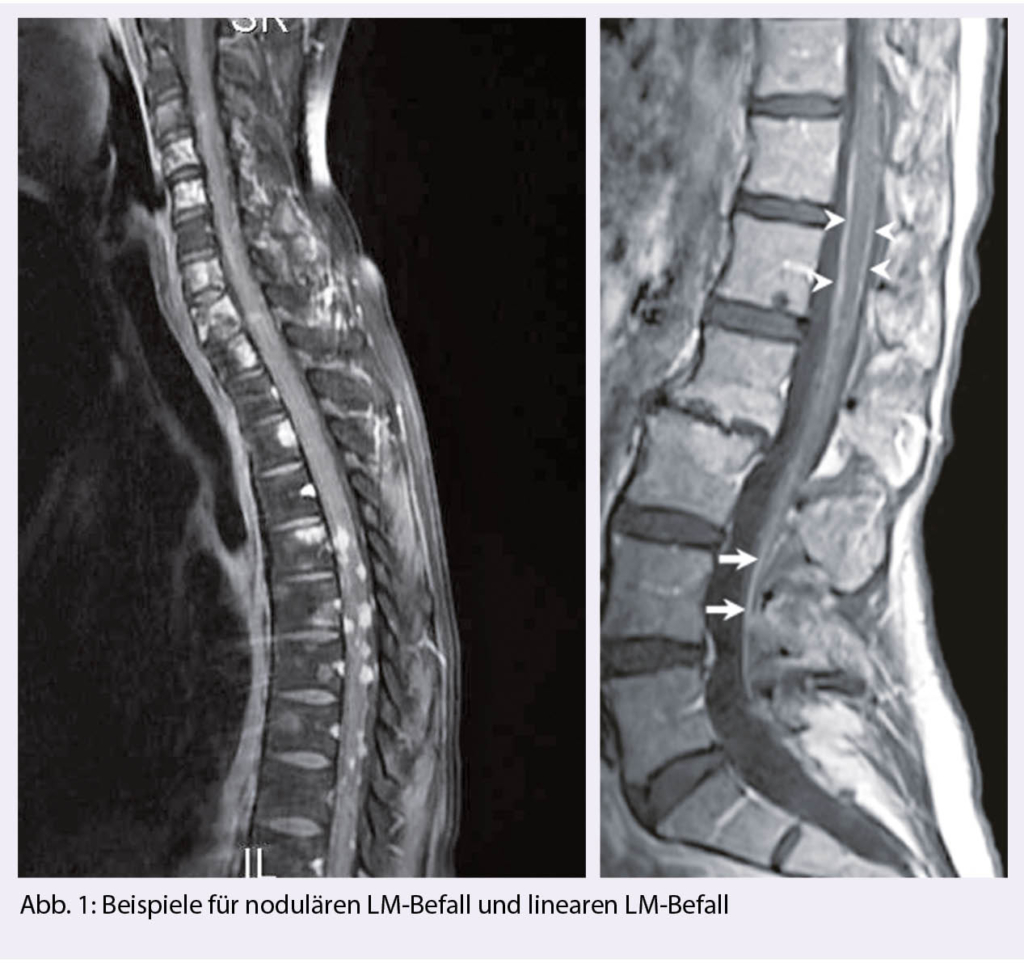

Man unterscheidet einen nodulären Tumorbefall, an den Meningen adhärent, eine tapetenartige Auskleidung der Meningen und frei flottierende Tumorzellen oder eine Kombination dieser Manifestationen (Abb. 1). Es ist nachvollziehbar, dass bei der nodulären, adhärenten Form, keine Tumorzellen im Liquor fassbar sein können.

Aus den verschiedenen Befallsarten ergeben sich therapeutische Konsequenzen. Bei ausgedehntem nodulären Befall bietet sich eine lokale Radiotherapie an, besonders, wenn die Liquorzirkulation gefährdet ist, Symptome vorliegen oder ein Hydrocephalus droht, wohingegen 1-2 mm schmale «Tapeten» oder frei zirkulierende Tumorzellen einer intrathekalen Therapie besser zugänglich sind. Ohne Therapie verläuft das leptomeningeale Wachstum innert weniger Wochen tödlich. Mit konventioneller Systemtherapie liegt das mediane Überleben bei etwa 3-6 Monaten. Zielgerichtete Therapien können langanhaltende Tumorkontrollen erreichen, besonders bei HER-2-positiven, EGFRmut und ALK- alterierten Tumorentitäten (1).